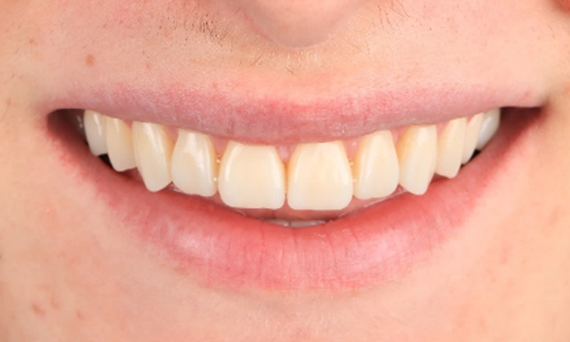

Before: Initial situation prior to orthodontic treatment.

After: Final result, 1 week post-operative.